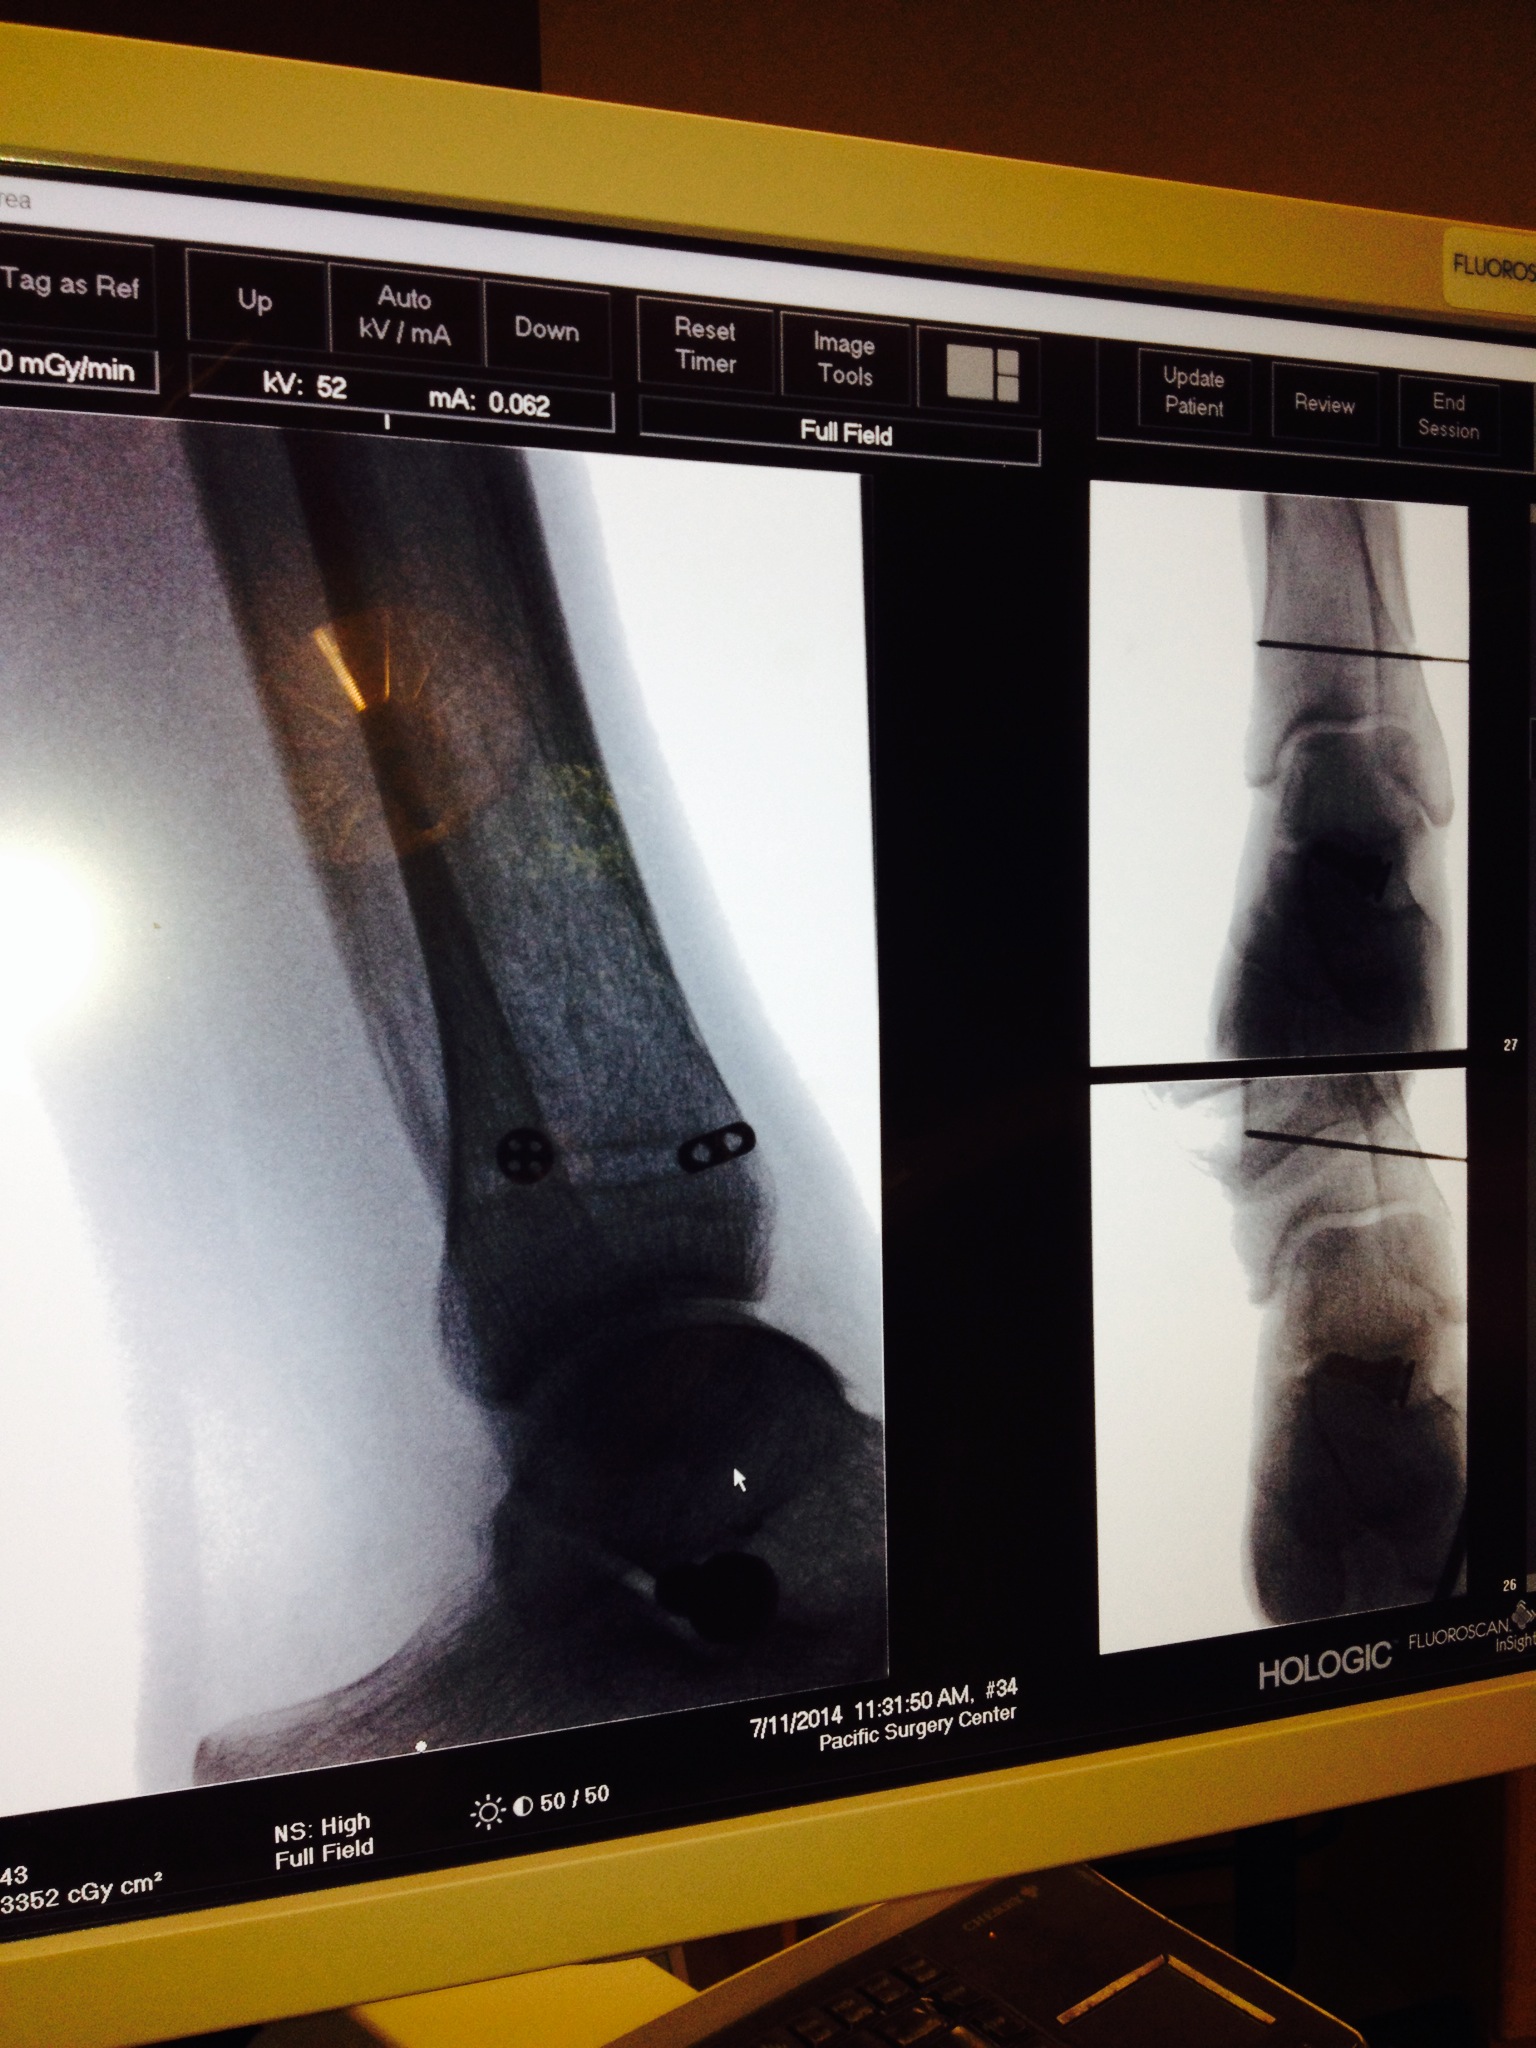

Here are photos (click on the photos to enlarge) taken during the Arthrex TightRope Dynamic Stabilization Surgery. I consider this surgery to be very minimally invasive. Only a couple of stitches in my lateral ankle/fibula bone. I was just a little over an hour and my husband was able to see me in recovery. I woke up as usual with no complications and I began my usual hunger spree of “Feed Me”. I did remember saying, “Why do I have to wake up, I don’t want too because I really didn’t want to face the reality of life in a non weight bearing status again.” For me surgery has always been the easy part. Life afterwards is the struggle.